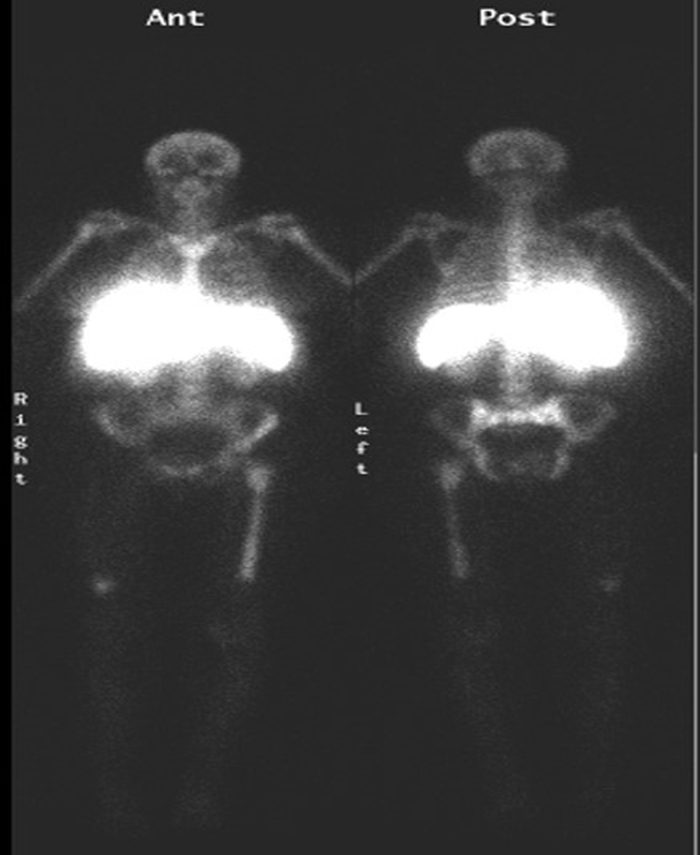

| 63 year-old woman with right femoral hardware for 3 years presented with right leg pain. Whole body Tc-99m HMPAO tagged WBC (A) scan demonstrated focal abnormal activity in the distal right femur which may represent infection or focal marrow. Tc99m sulphur colloid bone marrow scan (B) four weeks later demonstrates similar focal uptake in the distal right femur confirming the etiology as uptake in displaced marrow and not infection. |